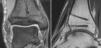

* Control radiológico a las 6 semanas en dos planos (fig. 14). Si el injerto se ha integrado correctamente, se incrementa progresivamente la carga hasta alcanzar la carga completa en torno a las 12 semanas.

Figuras 14a y b

Radiografías del tobillo en dos planos, a las 6 semanas de la intervención. Las cabezas de los implantes están recubiertas de fábrica con un marcador radioopaco, se identifican en la imagen como puntos. El bloque de hueso ha consolidado sin escalones y apenas se diferencia del hueso circundante. El cilindro está en una posición perfecta pero no se ha integrado completamente.

Las radiografías no mostraban ninguna evidencia de artrosis ni escalones a nivel del bloque óseo incorporado (fig. 16).

Figura 16